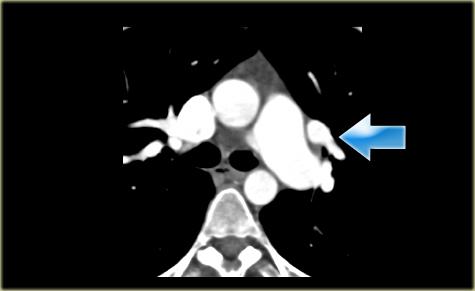

Describe the images on the left and then continue reading.

On the left side there is a vascular structure, that runs inferiorly below the level of the left hilum and enters into a dilated coronary sinus.

The diagnosis is left or double superior vena cava.

Left Superior Intercostal Vein.

This is an anastomosis between the accessory hemiazygos vein and the left brachiocephalic vein.

It courses along the lateral margin of the aortic arch (‘aortic nipple’).

It is a normal variant and if you look for this structure you will frequently notice it.

On the left a patient with a left superior intercostal vein.

Notice the ‘aortic nipple sign’.